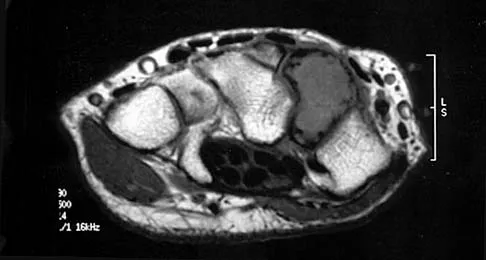

A 40-year-old man has a painful mass on his anterior ankle joint with limited range of motion. A radiograph, MRI scan, a gross specimen, and a hematoxylin/eosin biopsy specimen are shown in Figures 5a through 5d. What is the most likely diagnosis?